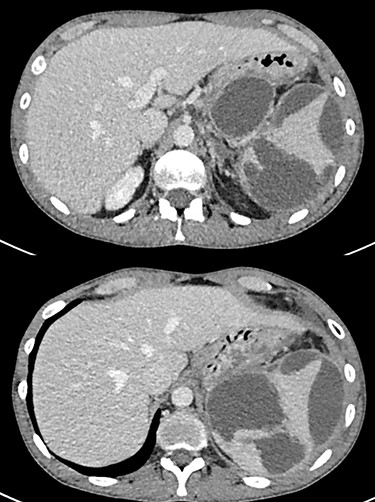

Due to patient stability, conservative management was decided. This included analgesics, antibiotics and nutritional optimization. During the first 48 h, the patient was stable, with little pain and without fever. On the fourth day of hospitalization, he developed tachycardia and severe pain. The abdominal examination showed signs of peritoneal irritation and laboratory tests with a white cell count of 41 × 109/L. Ultrasound assessment showed diffuse abdominal free fluid. An emergency laparotomy was performed, finding 1.5 L of dark serohematic and purulent fluid in the peritoneal cavity. The amylase level of this fluid was 3000 U/L. A large pancreatic tail pseudocyst was identified in addition to abundant clots in the left subphrenic space because of a ruptured spleen (Fig. 2). Due to extensive peripancreatic inflammation, dissection was difficult. Splenectomy was performed, extracting the shattered splenic parenchyma (Fig. 3). The amylase level of pancreatic cystic fluid was 13 000 U/L, confirming the diagnosis of a pseudocyst. We performed a double layer hand-sewn gastrocystic anastomosis with silk 2.0. One drain was located close to the anastomosis and two in the splenic bed. The patient had a satisfactory recovery, with drains fluid amylase level in the normal range, and was discharged on the 11th postoperative day.

Intraoperative image of the ruptured spleen associated with abundant clots.